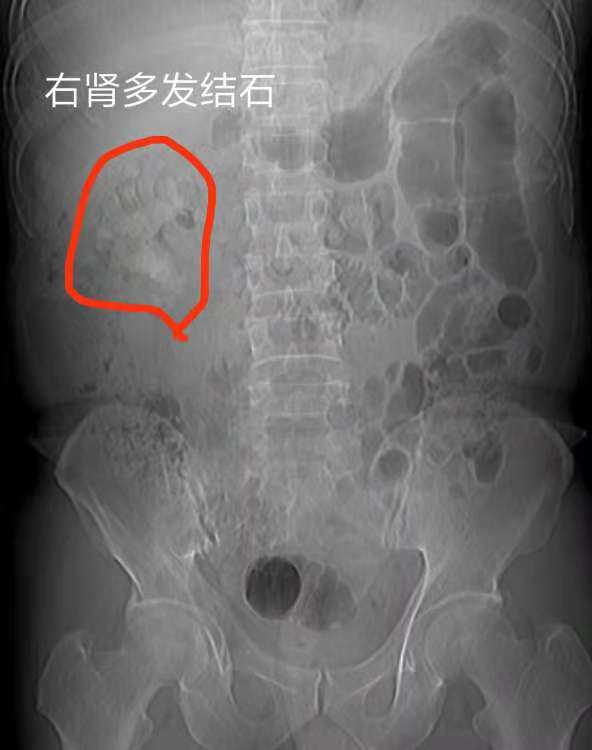

术前尿路平片